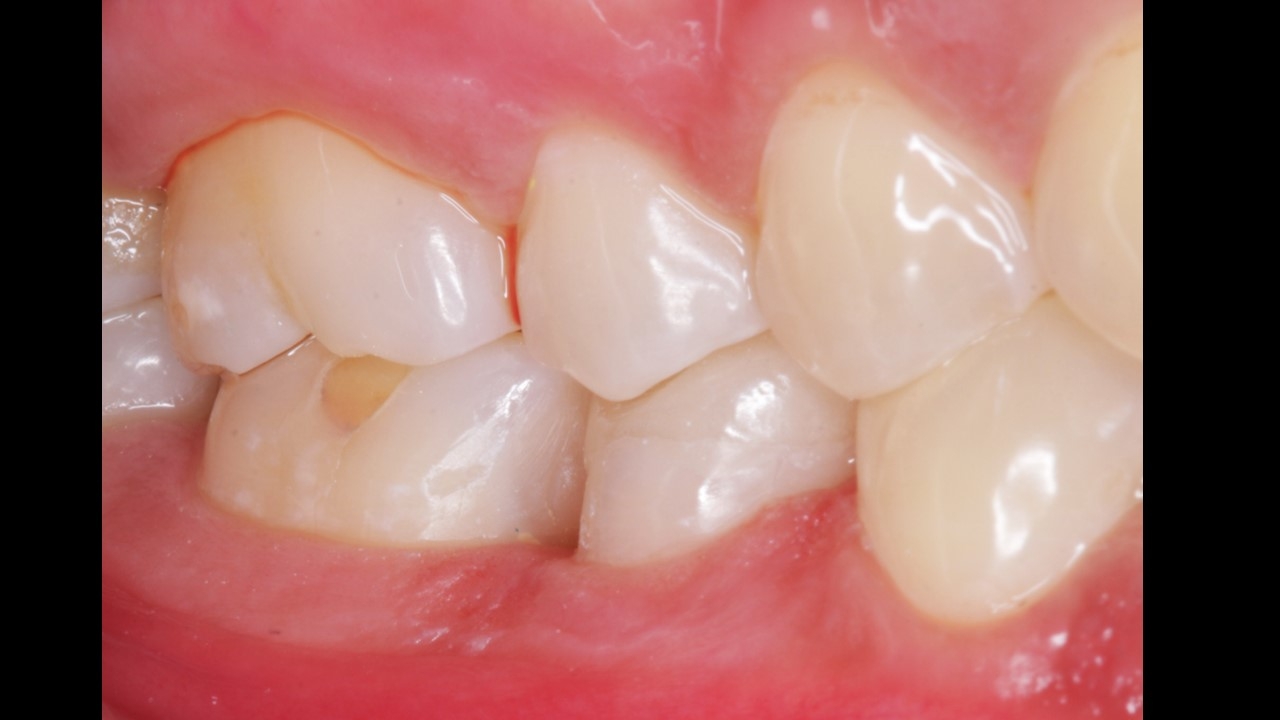

Patient presented with pain and discomfort in the lower right second premolar. Pain was of radiating type accompanied with food lodgement. On examination, the lower right 2nd premoalr was decayed with a portion of the distal surface lost due to the process of deacy. Examination alos revealed decay of the molar on the mesial side. Typical presentation that accompanies food lodgement and decay.

Root canal therapy (RCT)in lower right 2nd premolar and lower left 1st molar.

Post (fiber) and core , Emax onlay